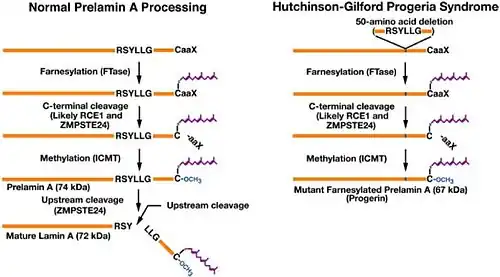

In the setting of ZMPSTE24 deficiency, the final step of lamin processing does not occur, resulting in an accumulation of farnesyl-prelamin A. In Hutchinson–Gilford progeria syndrome, a 50-amino acid deletion in prelamin A (amino acids 607–656) removes the site for the second endoproteolytic cleavage. Consequently, no mature lamin A is formed, and a farnesylated mutant prelamin A (progerin) accumulates in cells.[9] The nuclear lamina consist of a two-dimensional matrix of proteins located next to the inner nuclear membrane. The lamin family of proteins make up the matrix and are highly conserved in evolution. During mitosis, the lamina matrix is reversibly disassembled as the lamin proteins are phosphorylated. Lamin proteins are thought to be involved in nuclear stability, chromatin structure and gene expression. Vertebrate lamins consist of two types, A and B. Through alternate splicing, this gene encodes three type A lamin isoforms.[10]